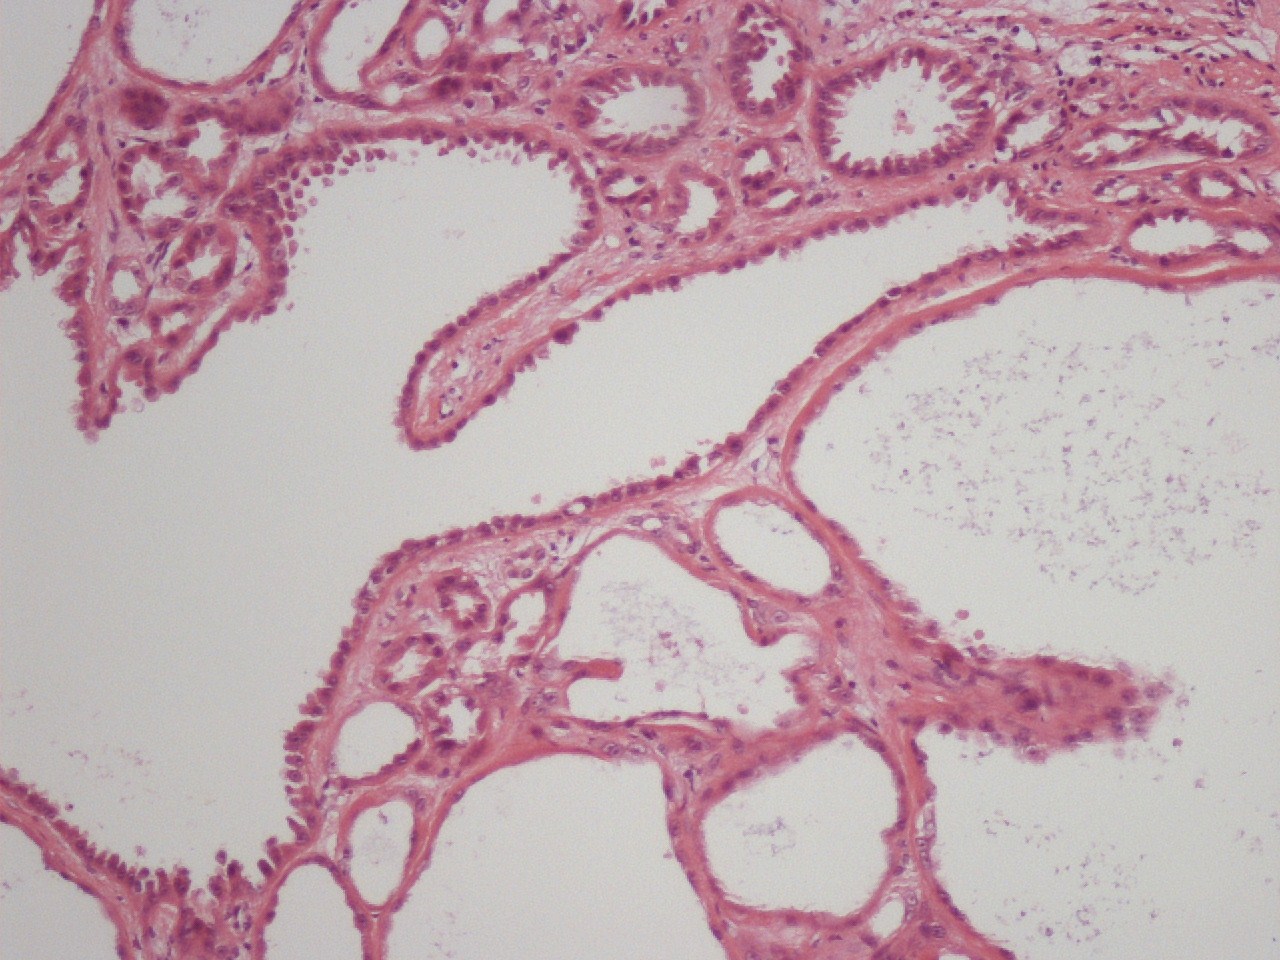

Case description (by case creator):

Renal tumor from a 48 year old male. The tumor was 7.3cms in diameter and had a grey spongy morphology. It is composed of cysts of varying sizes. These are lined by a single layer of tumor cells. these are variously cuboidal, columnar or on occasion hob-nailed. The cytoplasm is eosinophilic and faintly granular. Nuclei are centrally placed and although showing minimal pleomorphism do have prominent single nucleoli. Mitoses are rare.